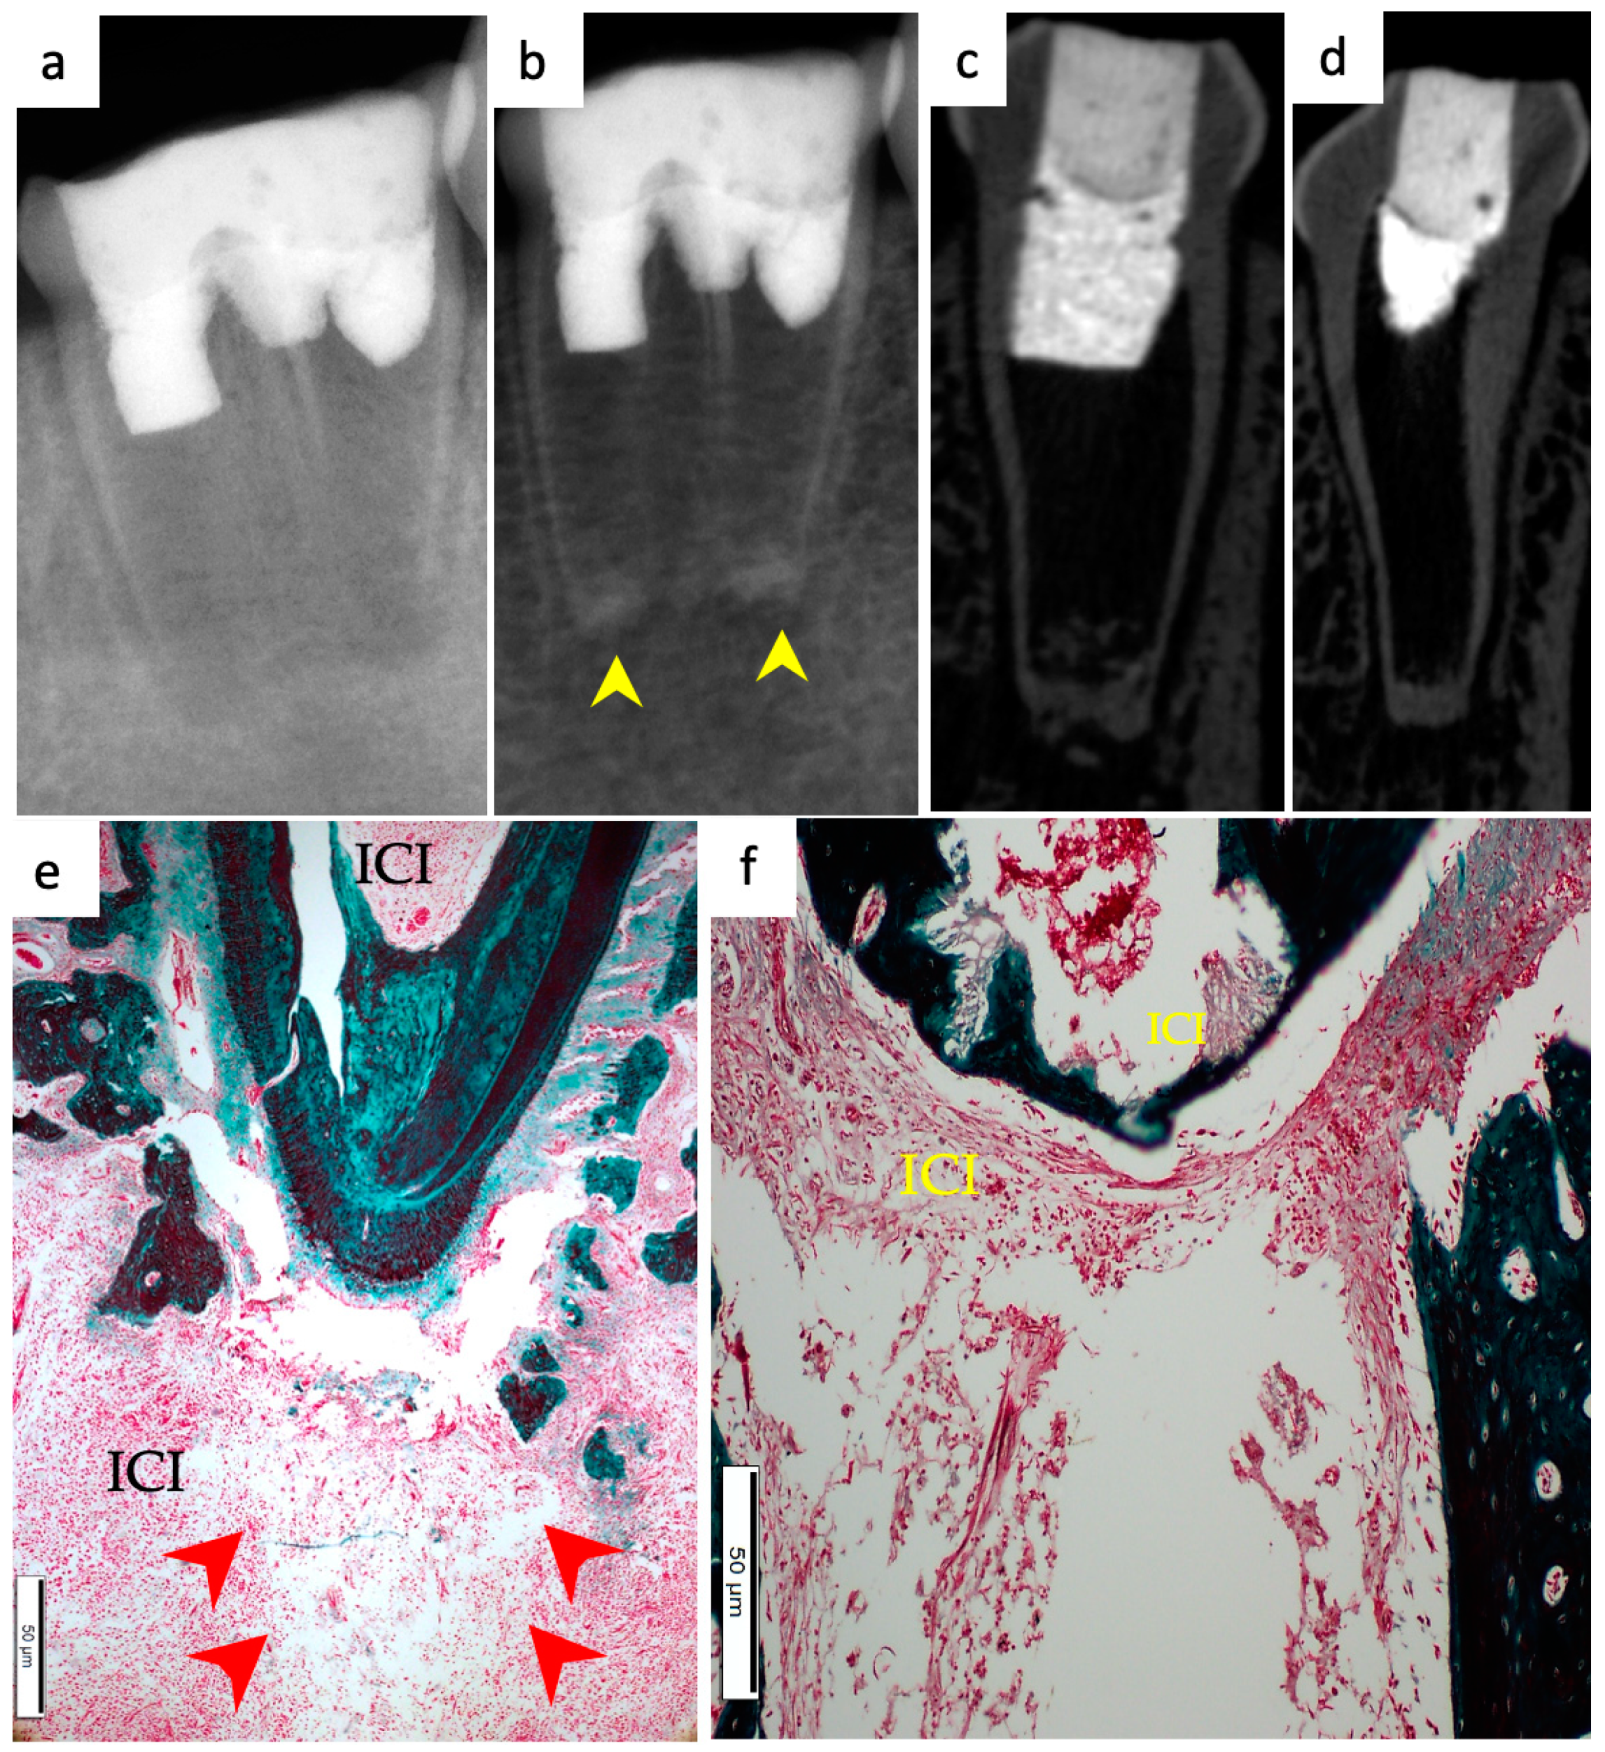

3.1. Hard Tissue Deposition

3.2. Type of Hard Tissue Formed

3.3. Vascularization and Formation of Vascularized Soft Connective Tissue

3.4. Degree of Inflammation

3.5. Apical Closure

3.6. Positive and Negative Control Groups